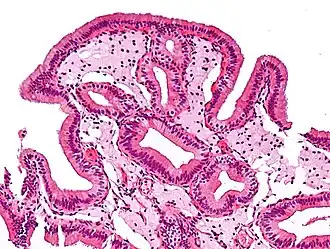

En medicina, la colesterolosis vesicular es la acumulación focal de histiocitos espumosos (macrófagos) cargados de colesterol en la lámina propia de la vesícula biliar.[1]

A veces se llama vesícula biliar de fresa por el aspecto punteado de la superficie de la mucosa en un examen general, similar al que presentan las fresas. La colesterolosis está causada por una acumulación anormal de depósitos de ésteres de colesterol en macrófagos dentro de la lámina propia (células espumosas) y en el epitelio de la mucosa. La vesícula biliar puede estar afectada de forma localizada o de forma difusa. La forma difusa se presenta macroscópicamente como una mucosa roja brillante con motas amarillas (debido a los lípidos), de ahí la comparación con la fresa. No está ligada a la colelitiasis (cálculos vesiculares) ni a la colecistitis (inflamación de la vesícula biliar).[2]

Micrografía de colesterolosis de la vesícula biliar -

Micrografía de colesterolosis de la vesícula biliar